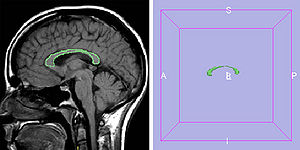

Treatment Planning and Delivery of Whole Brain Irradiation with Hippocampal Avoidance in Rats

Publication: PLoS One. 2015 Dec 4;10(12):e0143208. PMID: 26636762 | PDF Authors: Cramer CK, Yoon SW, Reinsvold M, Joo KM, Norris H, Hood RC, Adamson JD, Klein RC, Kirsch DG, Oldham M. Institution: Department of Radiation Oncology, Duke University Medical Center, Durham, NC, USA. Background/Purpose: Despite the clinical benefit of whole brain radiotherapy (WBRT), patients and physicians are concerned by the long-term impact on cognitive functioning. Many studies investigating the molecular and cellular impact of WBRT have used rodent models. However, there has not been a rodent protocol comparable to the recently reported Radiation Therapy Oncology Group (RTOG) protocol for WBRT with hippocampal avoidance (HA) which is intended to spare cognitive function. The aim of this study was to develop a hippocampal-sparing WBRT protocol in Wistar rats. Methods: The technical and clinical challenges encountered in hippocampal sparing during rat WBRT are substantial. Three key challenges were identified: hippocampal localization, treatment planning, and treatment localization. Hippocampal localization was achieved with sophisticated imaging techniques requiring deformable registration of a rat MRI atlas with a high resolution MRI followed by fusion via rigid registration to a CBCT. Treatment planning employed a Monte Carlo dose calculation in SmART-Plan and creation of 0.5 cm thick lead blocks custom-shaped to match DRR projections. Treatment localization necessitated the on-board image-guidance capability of the XRAD C225Cx micro-CT/micro-irradiator (Precision X-Ray). Treatment was accomplished with opposed lateral fields with 225 KVp X-rays at a current of 13mA filtered through 0.3 mm of copper using a 40x40 mm square collimator and the lead blocks. A single fraction of 4Gy was delivered (2Gy per lateral field) with a 41 second beam on time per field at a dose rate of 304.5 cGy/min. Dosimetric verification of hippocampal sparing was performed using radiochromic film. In vivo verification of HA was performed after delivery of a single 4Gy fraction either with or without HA using γ-H2Ax staining of tissue sections from the brain to quantify the amount of DNA damage in rats treated with HA, WBRT, or sham-irradiated (negative controls). Results: The mean dose delivered to radiochromic film beneath the hippocampal block was 0.52Gy compared to 3.93Gy without the block, indicating an 87% reduction in the dose delivered to the hippocampus. This difference was consistent with doses predicted by Monte Carlo dose calculation. The Dose Volume Histogram (DVH) generated via Monte Carlo simulation showed an underdose of the target volume (brain minus hippocampus) with 50% of the target volume receiving 100% of the prescription isodose as a result of the lateral blocking techniques sparing some midline thalamic and subcortical tissue. Staining of brain sections with anti-phospho-Histone H2A.X (reflecting double-strand DNA breaks) demonstrated that this treatment protocol limited radiation dose to the hippocampus in vivo. The mean signal intensity from γ-H2Ax staining in the cortex was not significantly different from the signal intensity in the cortex of rats treated with WBRT (5.40 v. 5.75, P = 0.32). In contrast, the signal intensity in the hippocampus of rats treated with HA was significantly lower than rats treated with WBRT (4.55 v. 6.93, P = 0.012). Conclusion: Despite the challenges of planning conformal treatments for small volumes in rodents, our dosimetric and in vivo data show that WBRT with HA is feasible in rats. This study provides a useful platform for further application and refinement of the technique. Funding:

MRI with labeled structures from atlas registered to the CBCT. Registration was carried out with the open source imaging tool 3D Slicer, Version 4.4.0. |